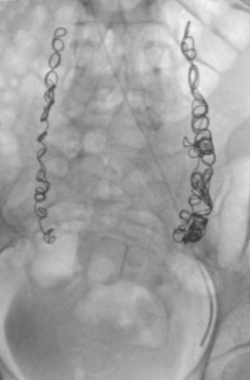

"Ante todos estos hallazgos, la flebografía, técnica radiográfica para la valoración mediante contrastes de los distintos territorios vasculares afectados, continúa siendo el patrón de oro para el diagnóstico del síndrome de congestión pélvica. Empleando fluoroscopia, a través de un pequeño catéter menor de 2 milímetros, se introduce desde el brazo derecho contraste selectivo sobre las venas ováricas y las venas ilíacas internas para evidenciar las varices pélvicas y determinar los patrones de reflujo y/u obstructivos", explica el Dr. Puras.

Para este prestigioso cirujano vascular "la embolización pélvica de las venas afectadas ha probado ser exitosa y segura en los últimos tiempos, con una evolución prometedora del dolor, reduciéndolo hasta en un 85% a un plazo de 2 años, con la ventaja de no encontrarse cambios significativos en cuanto al ciclo menstrual y la fertilidad a largo plazo en las mujeres tratadas. El procedimiento, mínimamente invasivo y relativamente rápido, consiste en cerrar las venas afectadas evitando que se desarrollen otras nuevas varices."